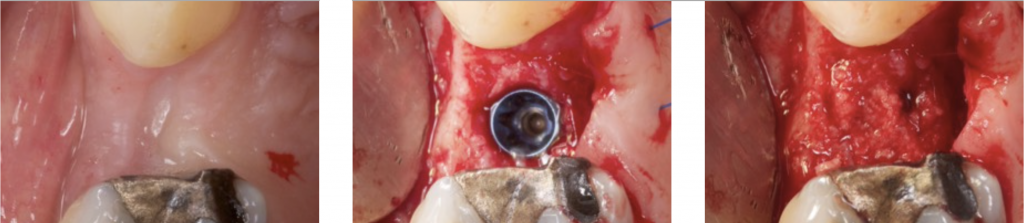

3) DEHISCENCE- TYPE DEFECT: CLASS 2

It is characterized by dehiscence in which the adjacent bone walls provide the volume of the area to be augmented.

Dehiscence of the buccal wall during the implant placement is the most frequent complication.

So, guided bone regeneration of this kind of defect is well documented in the scientific literature (Palmer 1998).

We can say that the regeneration in this kind of defect is very predictable (Kohal 1999).

In posterior and in aesthetically sensitive sites, regeneration with particulate bone substitutes and a resorbable membrane is the treatment of choice. This will provide volume augmentation in the buccal wall.

Some perforations can be performed in the cortical bone to improve bone repair and vascularization of the graft (Rompen 1999).

Particulate bone is applied on the exposed implant surface, and a membrane is shaped and adapted to extend 2 mm beyond the defect margins.

Also, autogenous bone can be applied as a first layer over the implant surface. This will provide two missing properties in the xenograft: Osteogenic and osteoinductive.

After applying the autogenous bone layer, another layer of the particulate bone substitute is placed, and finally, a resorbable membrane covers the bone substitute.

This technique is named the "Sandwich Bone Augmentation Technique" (Hom-Ley Wang 2004). To perform this technique, a membrane is mandatory (Jia-Hui Fu 2013).

During healing, there are compressive forces that will collapse the regenerated site. We should always perform an over-augmentation because shrinkage of the overall volume must be anticipated.

Additional fixation should be provided to stabilize the grafted area. This can be done with fixation pins, suturing the membrane, double-layer technique, or the healing cap.